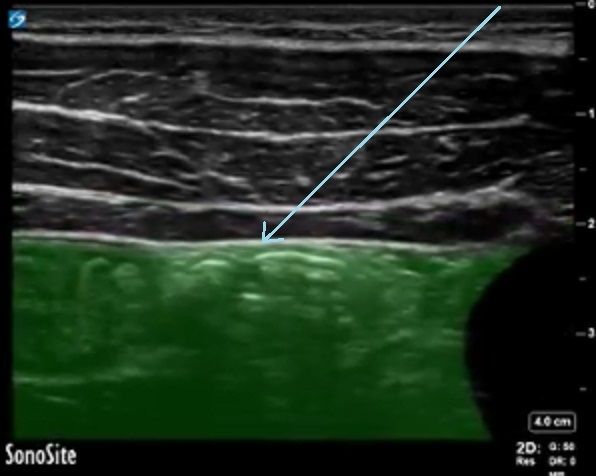

TAP Abdominal Cavity Highlighted Image

Blue Arrow: Peritoneum

Highlighted Area: Abdominal Cavity